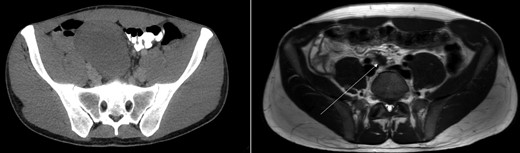

Axial view of CT-abdomen (left) and MRI-abdomen 1 year later. A pear-shaped lesion is seen on the CT, which regressed as seen on the MRI (arrow).

Sonography after three months showed a reduction in size to 9.4 × 5.4 cm2. On request of the patient, who was anxious of having a tumor which was treated conservatively, a second opinion was performed at an University Medical Center. They acknowledged the conservative approach and advised follow up with magnetic resonance imaging (MRI) 1 year after diagnosis. This MRI showed regression of the tumor with a small residue of 2.2 × 1.2 × 1.9 cm2 (Figs 1 and 2) along the right ureter and a minimal hydronephrosis of the right kidney without loss of renal function. A second MRI 6 months later and a third MRI 1 year later showed persisted regression without hydronephrosis. Both scans showed no other masses. The patient did not develop any symptoms during follow up.